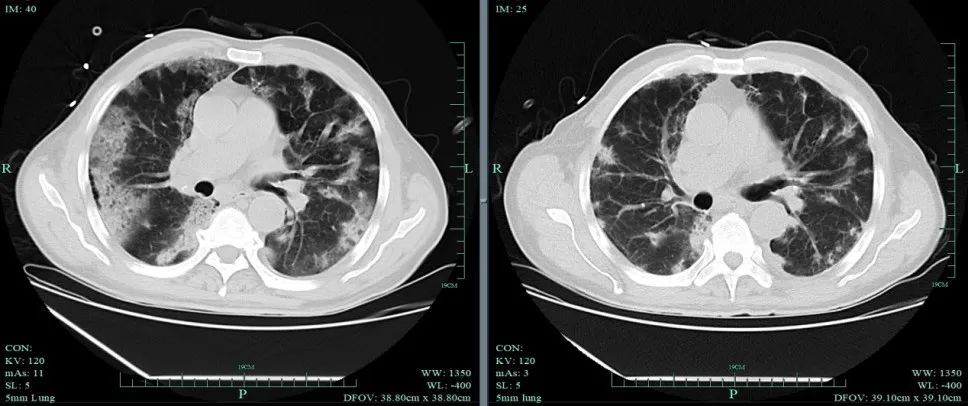

浙大一院感染病科近期接诊一例感冒一周拖成肺炎的中年患者,双肺存在湿啰音,肺部CT显示多发斑片状高密度影,属于典型的重症肺炎。

肺炎是流感最常见的并发症,典型表现是咳嗽伴呼吸困难、呼吸急速(>24次/分)、缺氧和发热(>3天)。肺炎类型包括:

原发流感病毒性肺炎:流感发作3~5日后仍持续存在高热,以及有上述肺炎表现。通常很严重,进展可能很快,不积极干预会有生命危险,特别是有肺部或心血管疾病的人群。